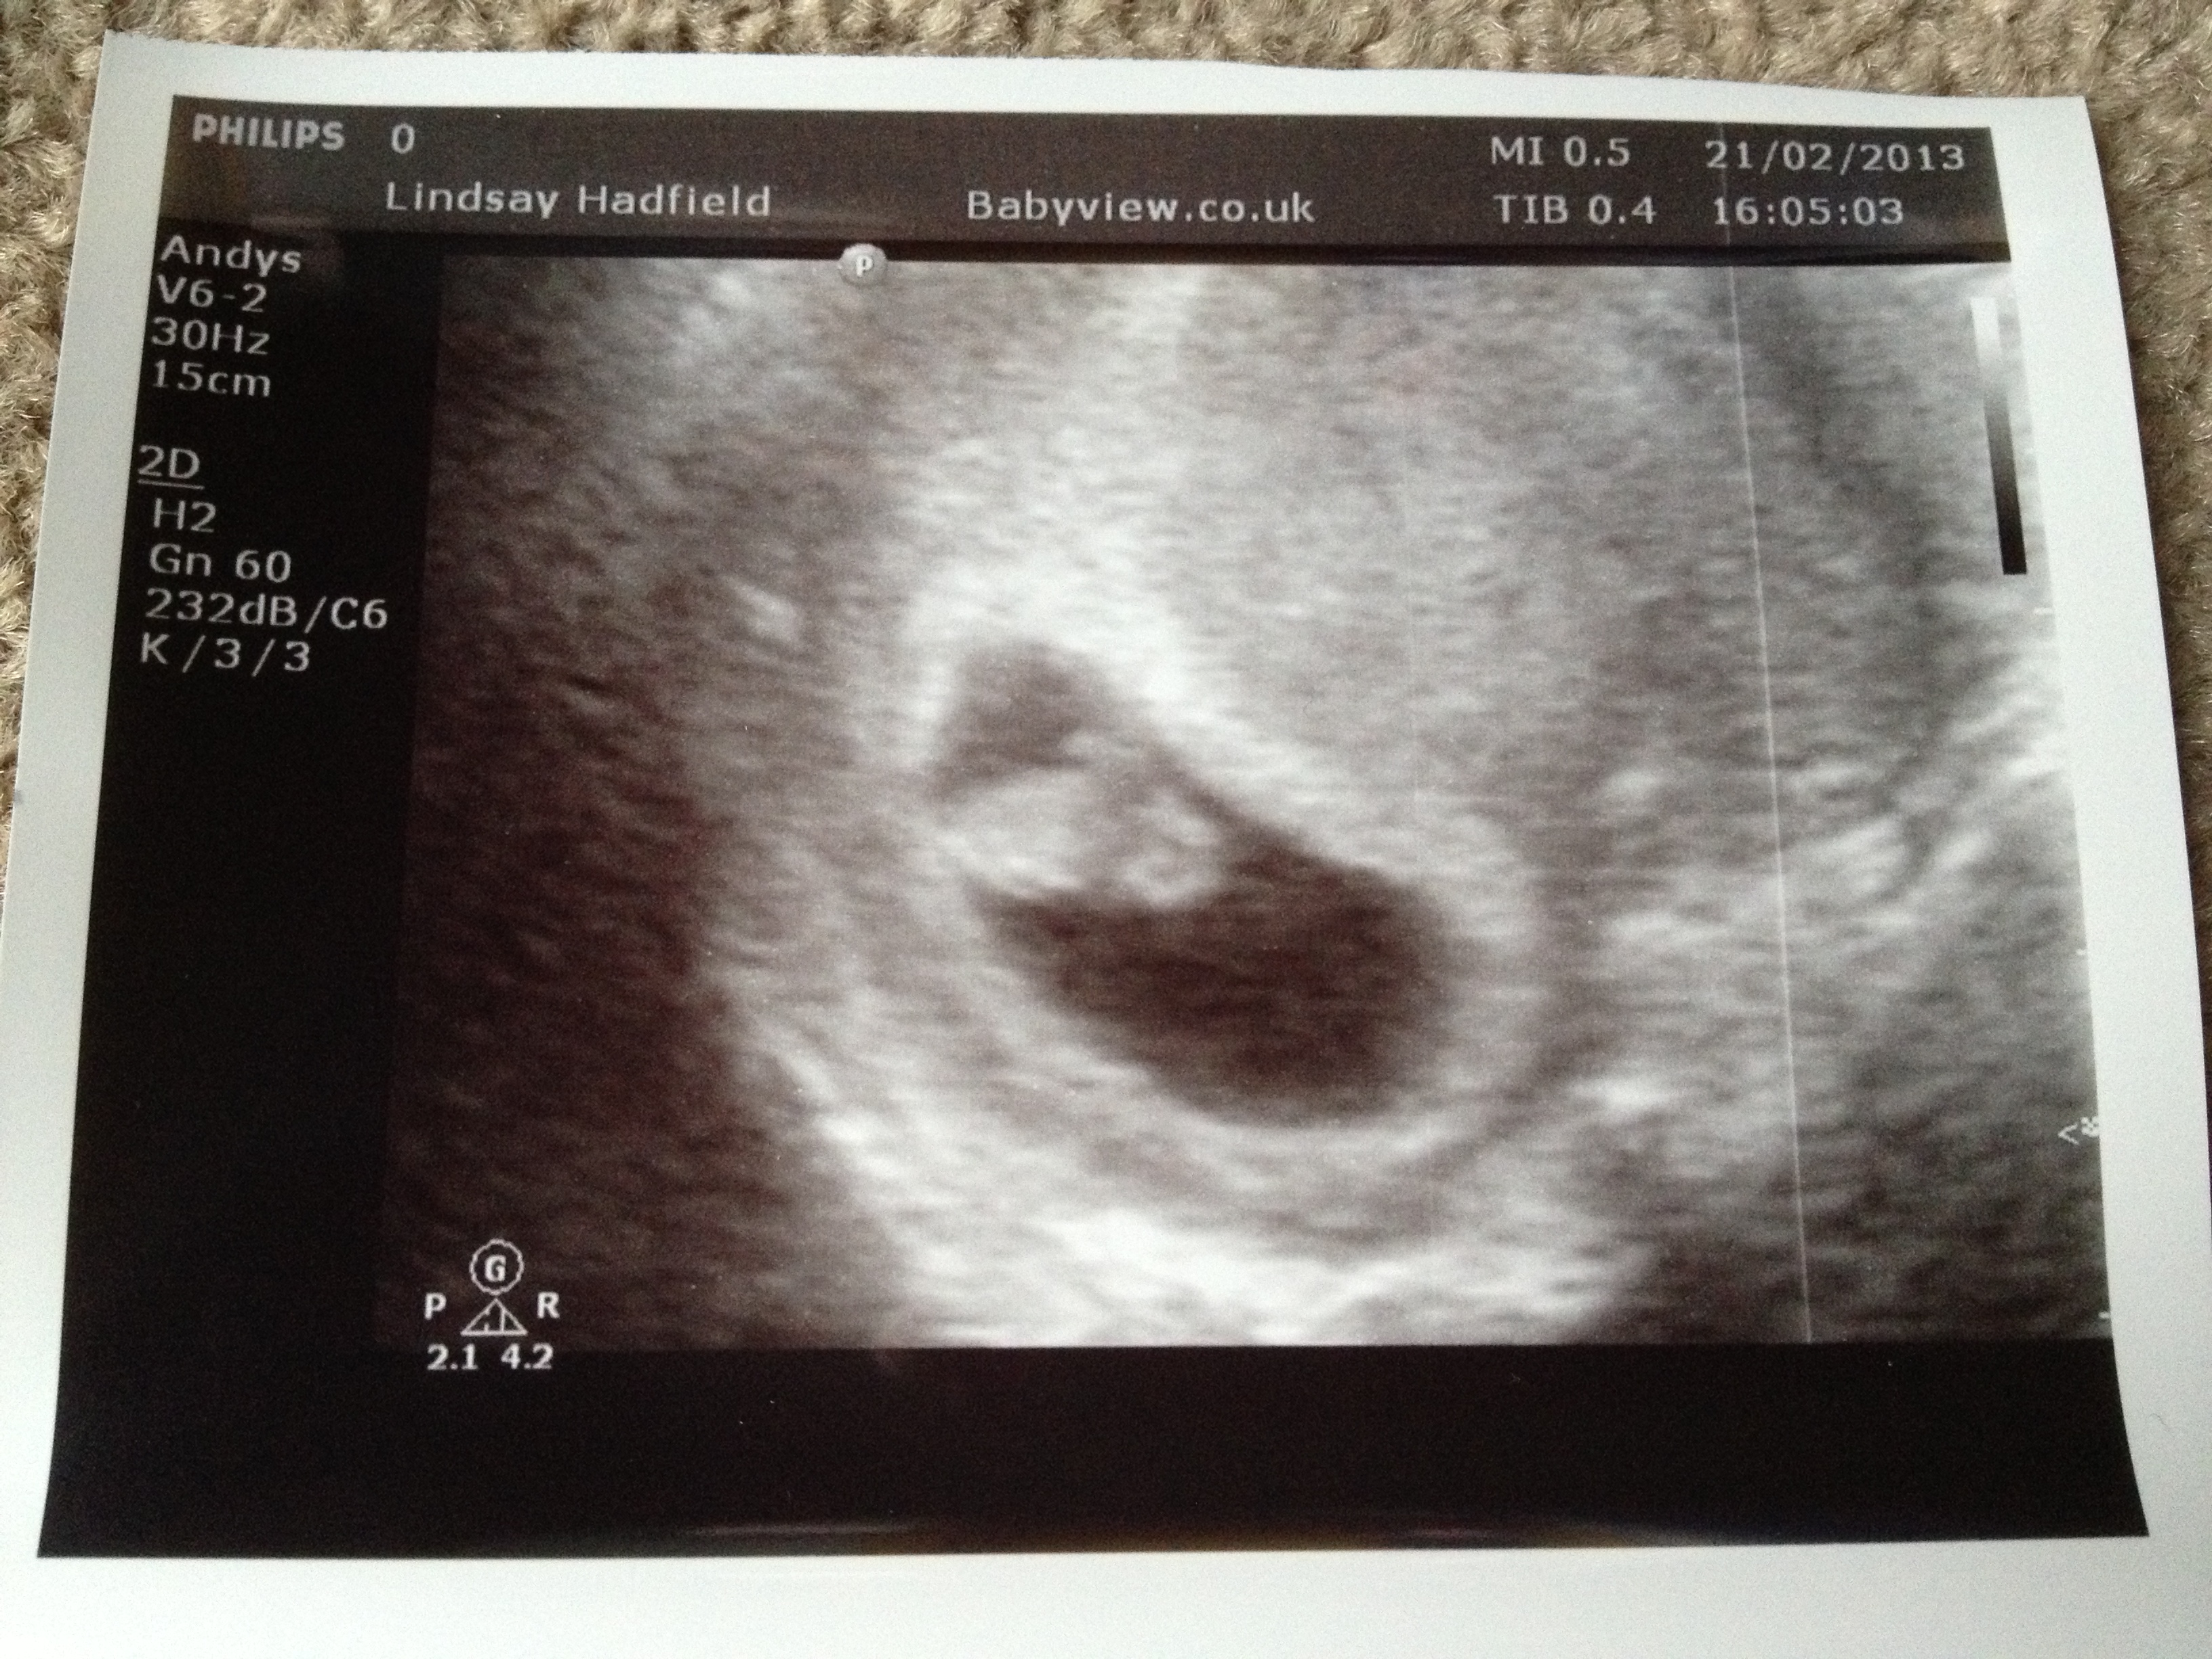

Predictions please?? 8, 11 and 13 weeks